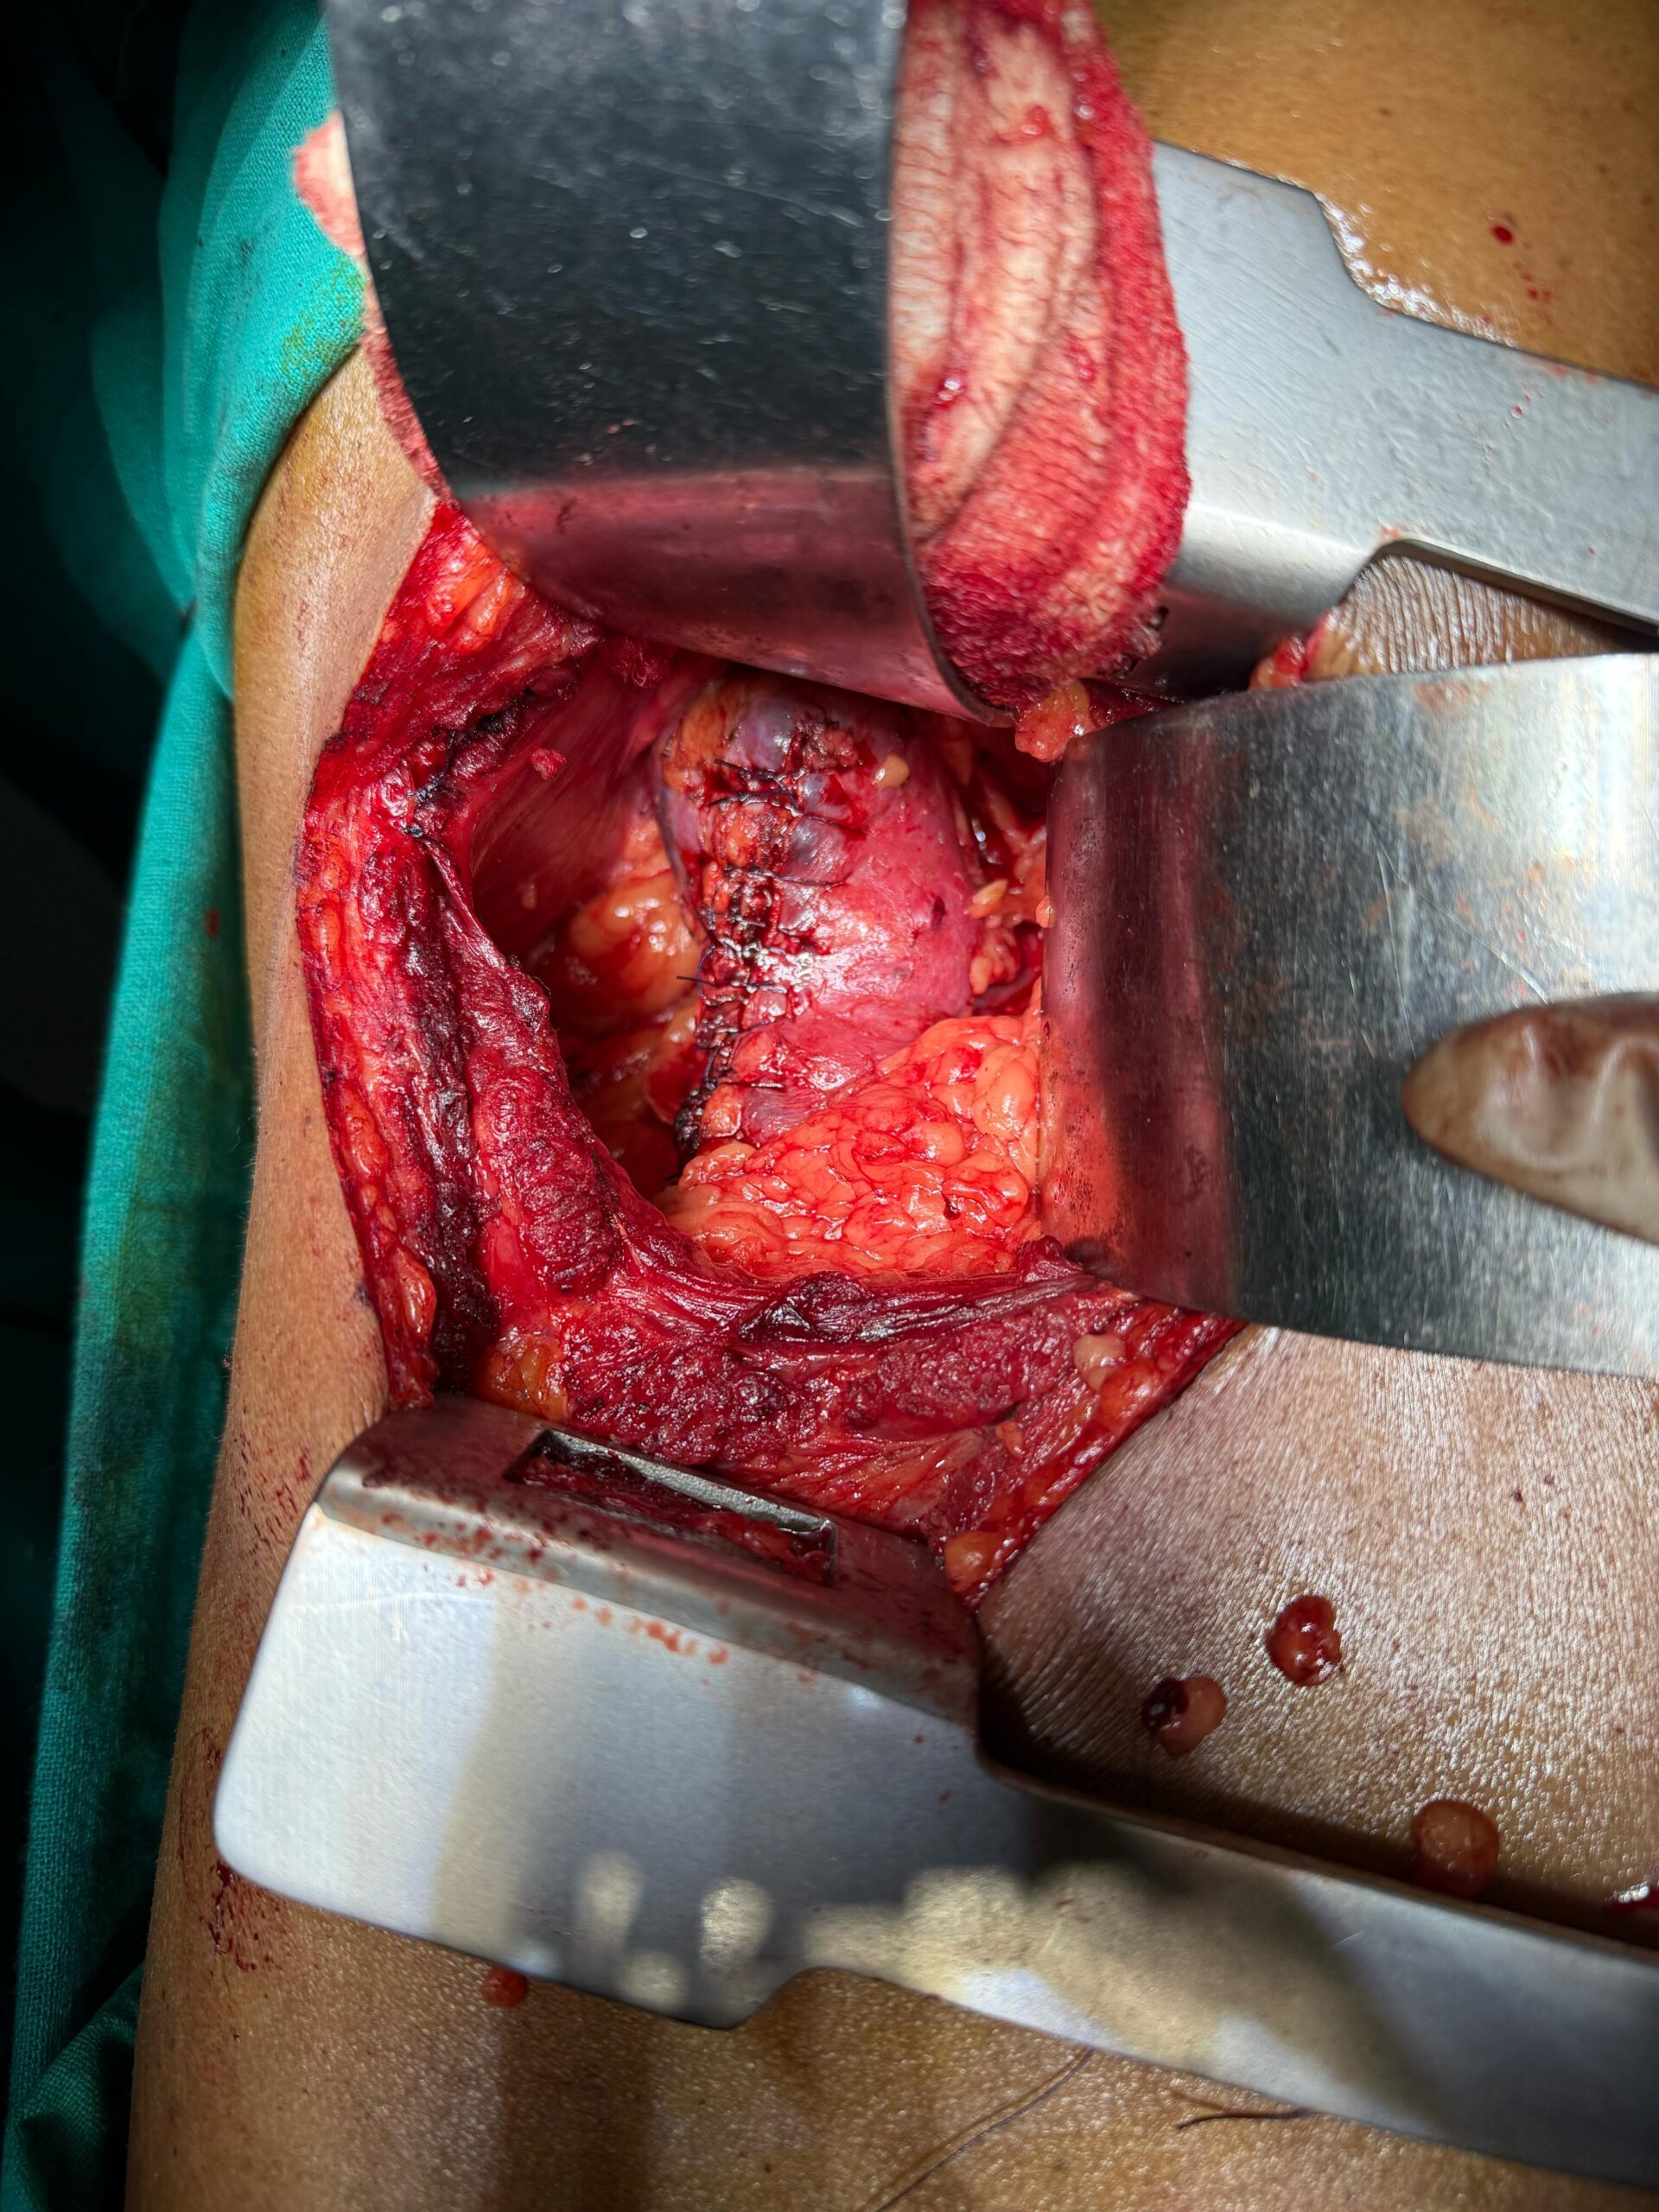

Our Gallery